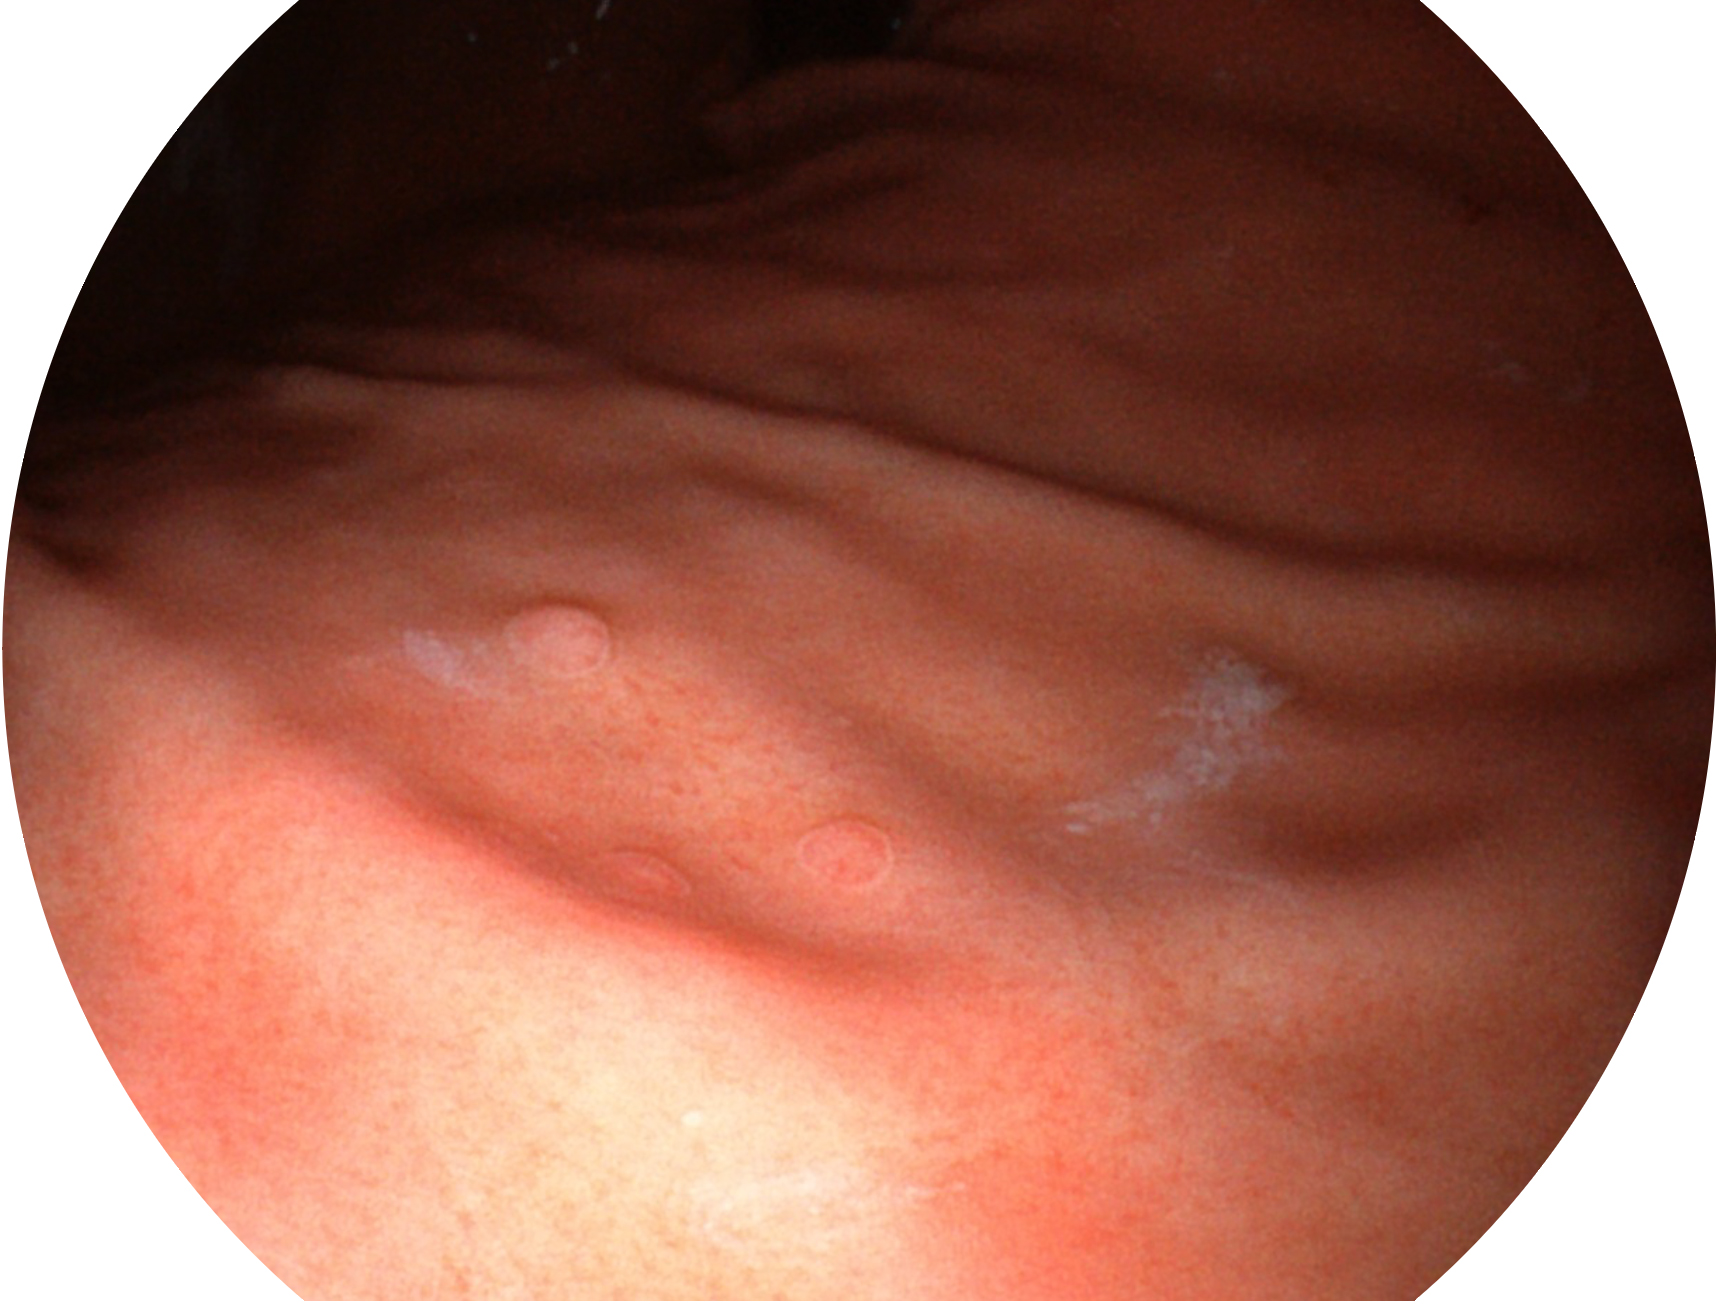

milan米兰新开发的内镜染色技术,主要是基于多波长LED 光源的开发,VLS-55Q 四波长LED 光源是由四个不同颜色的LED光按照相应照明模式所规定的特定发光比例进行合束后形成,合束后形成的照明光的光谱由红光、绿光、蓝光及蓝紫光这四个不同的波段范围构成。具有更高光谱自由度,通过光谱比例的控制,实现了聚谱成像技术,英文全称为“Spectral Focused Imaging, SFI”,缩写为“SFI”和光电复合染色成像技术,英文全称为“Versatile Intelligent Staining Technology, VIST”,缩写为“VIST”。